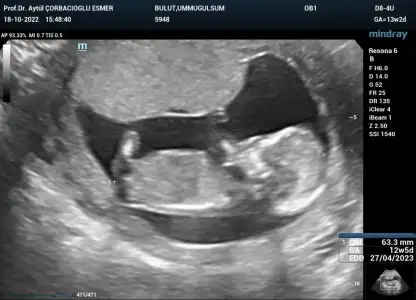

Selamlarrr, kontrolden çıktık, ikili test verdik. Ultrason detaylı bakıldı sağlıklı şimdilik kan verdik ama hâlâ cinsiyet net değil :110:

• 8F6EE475-BE71-414D-AF91-D23F9ECC390B.webp

8F6EE475-BE71-414D-AF91-D23F9ECC390B.webp

36,5 KB · Görüntüleme: 83